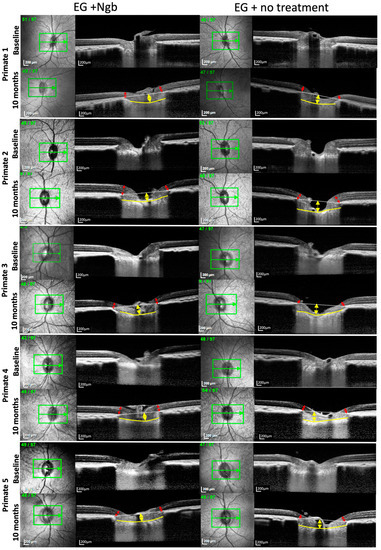

3.3. OCT Structural Changes with EG: Before and after Intervention